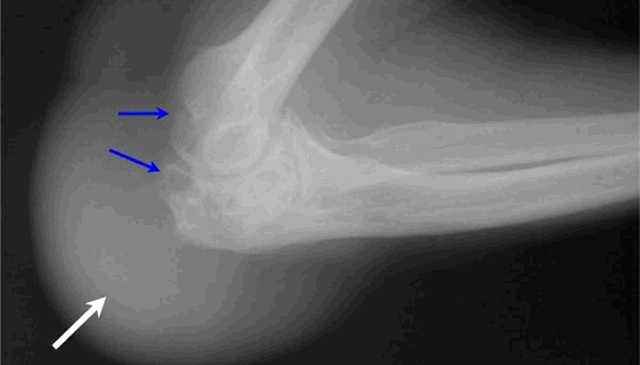

Диагноз бурсита локтевой сумки становится очевидным после осмотра пациента. Диагноз настолько очевиден, что не требуется использование специальных методов обследования, за исключением рентгенограммы (снимка) локтевого сустава в боковой проекции.

Рентгенограмма требуется не для установления диагноза, а для того чтобы оценить состояние локтевого отростка локтевой кости. Иногда вследствие травмы или хронического воспаления на локтевом отростке образуется остеофит (костный шип).

Остеофит часто дополнительно травмирует локтевую сумку, поддерживая воспаление. Рентгенограмма помогает решить вопрос о выборе метода лечения бурсита локтевой сумки. Если остеофит на локтевом отростке достаточно больших размеров, то целесообразно выполнить хирургическое лечение бурсита с резекцией остеофита.

Рентгенография локтевого сустава проводится, чтобы исключить перелом или присутствие инородного тела. На простых рентгеновских снимках также можно обнаружить кальцификаты - отложения солей кальция при хронических заболеваниях.[7]